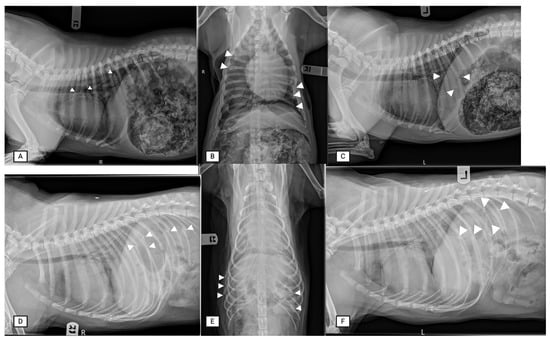

Ultrasound allowed for the detection of external greenstick fractures (GSFs) when performed by an expert, with sensitivity and specificity of 100% for both. Internal GSFs were more challenging to identify via the expert sonographer, with a sensitivity and specificity of 50% and 100%, respectively (n = 8). The expert radiologist did not differentiate between greenstick fracture and complete fractures and called all fractures complete. Similarly, both radiography and ultrasound had similar positive and negative predictive values for the identification of complete rib fractures, whether performed by experts or novices (Table 1). False positives were rare, only occurring twice. There were two false positive GSFs, one of which was a CF on necropsy. In both cases, adjacent ribs were positive for fractures. Radiographs detected rib fractures with better accuracy in two cases, both involving a rib with two fractures where only one was detected on POCUS. Lastly, on radiographs, fractures overlying the diaphragmatic crura (zone 3), or those present in the mid dorso-ventral part of the rib, where the convexity of the rib meets the body wall (seen on ventro-dorsal radiograph zone 3), also had occasional missed fractures (Table 2, Figure 6).

Table 2.

Detection of rib fractures by radiography compared between novice and expert with necropsy as the reference standard. Sensitivity (Se), specificity (Sp), negative predictive value (NPV), positive predictive value (PPV) and accuracy reported in percentages. Zones 1, 2 and 3 correspond to the zones described in Figure 1.

Figure 6.

Radiographic evaluation of rib fractures. Three-view thoracic radiographs (right lateral radiographs (A,D), ventro-dorsal (B,E) and left lateral radiographs (C,F) were taken. The points of the white arrowheads show the rib fracture.